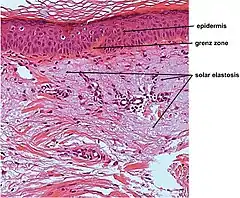

Elastosis

Elastosis is the buildup of elastin in tissues, and is a form of degenerative disease.[10] There are a multitude of causes, but the most commons cause is actinic elastosis of the skin, also known as solar elastosis, which is caused by prolonged and excessive sun exposure, a process known as photoaging. Uncommon causes of skin elastosis include elastosis perforans serpiginosa, perforating calcific elastosis and linear focal elastosis.[10]

| Actinic elastosis (most common, also called solar elastosis) |

Elastin replacing collagen fibers of the papillary dermis and reticular dermis |  |